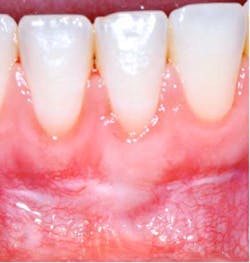

Depending on the severity and extent that the mucogingival defects present, we often administer a hybrid/combination therapy. Many of our patients previously experienced mucogingival grafting procedures at other offices, searched the Internet, or discussed with friends who have had soft-tissue grafts, and as a result they are extremely fearful of the dreadful “pizza burn” that one may experience after harvesting from the palate. As reported in the literature and confirmed clinically in our office, with the addition of an enamel matrix protein, patients consistently report minimal postoperative swelling and discomfort. This has been a huge game changer for our practice and will be for yours too (figure 3). (7)

There is certainly no panacea for treatment, but we have found this combination therapy provides our patients with long-term predictable, stable results. Our preferred treatment method for gingival recession defects affecting one to four teeth is to use a tunneling technique in combination with a subepithelial connective tissue graft, enamel matrix derivative, and a coronally advanced flap (figures 4-9). When treating four or more teeth, or if a patient is opposed to harvesting a SCTG, we use a tunneling procedure in conjunction with an acellular dermal matrix graft, enamel matrix derivative, and a coronally advanced flap.

The addition of a biologic agent, specifically enamel matrix derivative, and our combination therapy has allowed us to minimize previously experienced discomfort at the graft site and predictably treat problems affecting more than 50% of our adult patients. Now it is your turn to eliminate those “long in the tooth” problems and recession-proof your practice!